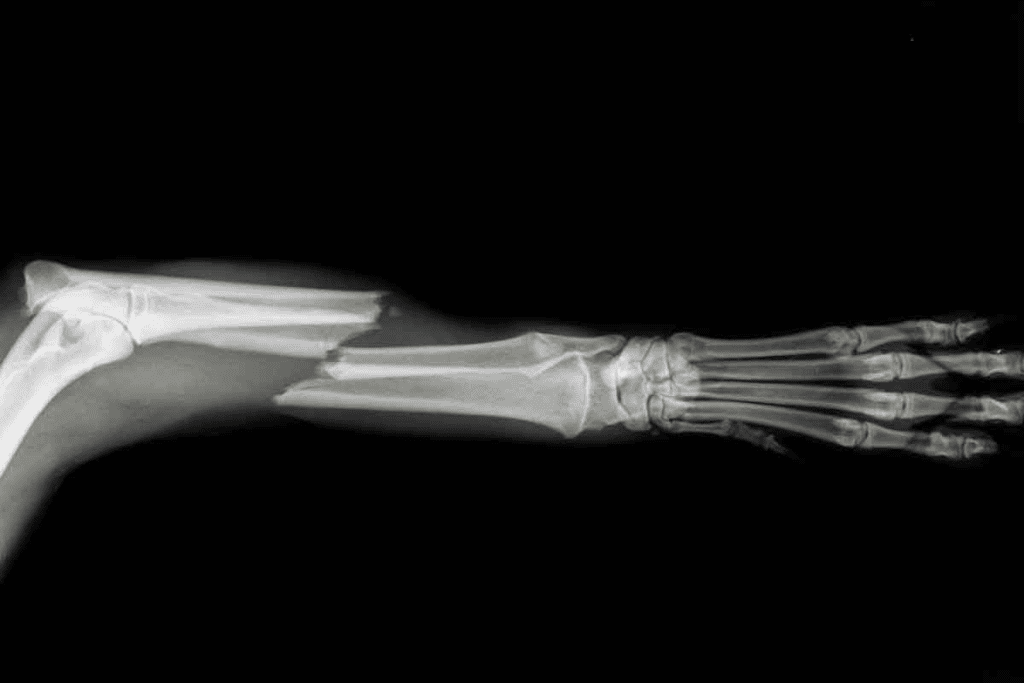

X-ray Imaging: Capabilities and Limitations

Knowing how X-rays work is ketor spotting bone fractures. X-rays are a mainstay in medical imaging for finding bone breaks. We’ll look at how X-rays spot fractures and their limits.

How X-rays Detect Bone Fractures

X-rays use beams that go through the body. Different tissues absorb these beams at different rates. Bones, being denser, absorb more, showing up white on the image. Soft tissues appear gray.

When a bone breaks, the X-ray shows it. The break in the bone is clear. The success of X-rays in finding fractures depends on several things:

For many fractures, X-rays are enough. But some fractures are hard to spot with X-rays alone.

When X-rays Fall Short

X-rays work well for many fractures. But they can miss some. Tiny or hairline fractures might not show up. Also, fractures in tricky spots like the spine or wrist can be tough to see with X-rays.

In these cases, more tests might be needed. MRI can give a clearer picture of bones and soft tissues. This helps find fractures X-rays can’t see.

Small Bone Fractures (Wrist, Ankle, Foot)

MRI is better than X-rays for finding small bone fractures. It spots tiny fractures and stress fractures that X-rays miss. This helps in treating these injuries right.